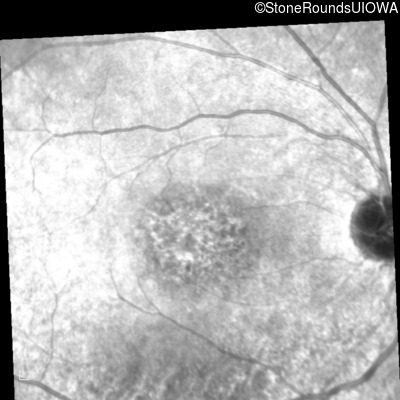

Infrared Fundus Photograph - Right - 20/40 -2 sc

Exemplar